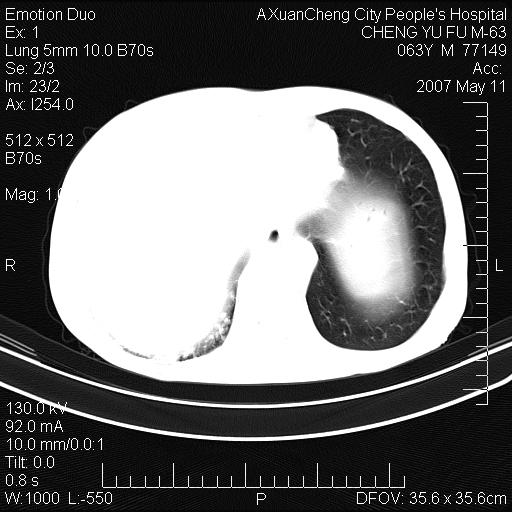

以下是引用小初学者在2007-5-11 19:32:00的发言:[br]1、首先考虑干酪性肺炎支气管播散[br]2、支气管肺泡癌待排

以下是引用zhangzhongshou在2007-5-11 19:30:00的发言:[br]细支气管肺泡癌可能性大。